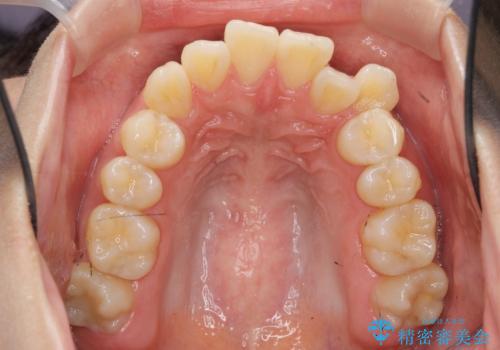

- 八重歯・がたつきのある歯並びの改善を求めて来院されました。

全部の歯が入り切るスペースがなかったため、小臼歯4本を抜去しワイヤーを用いたマルチブラケット矯正を選択しました。

歯並びの改善と共に、歯ブラシがしやすくなった!と喜んでいただくことができました。